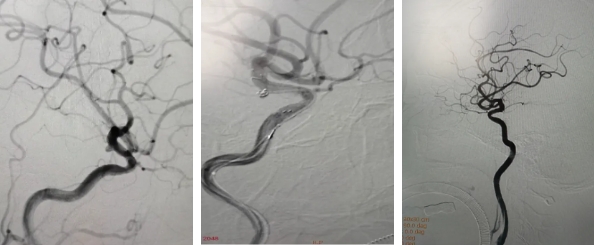

血管內(nèi)介入栓塞術(shù)(顱內(nèi)動(dòng)脈瘤介入栓塞術(shù))是神經(jīng)外科、介入科新興治療方法,在無需開顱暴露病灶的情況下借助影像設(shè)備的引導(dǎo),以動(dòng)脈血管做通道,把栓塞材料送入動(dòng)脈瘤腔內(nèi)將動(dòng)脈瘤閉塞,使動(dòng)脈瘤排除在血流之外從而達(dá)到治療目的。

動(dòng)脈瘤位于大腦中動(dòng)脈分叉部,屬血流沖擊部位,雖尚未破裂,但形態(tài)不規(guī)整,瘤體有分別突向前、后方的小突起,呈分葉狀。提示未來存在破裂風(fēng)險(xiǎn)。與患者溝通病情后,患者出于對(duì)動(dòng)脈瘤破裂出血風(fēng)險(xiǎn)的恐懼,積極要求行手術(shù)治療。

擬在支架輔助下行彈簧圈栓塞手術(shù)。

手術(shù)成功,整個(gè)操作不超過30分鐘,最大程度減少血管的刺激和對(duì)血流的影響。